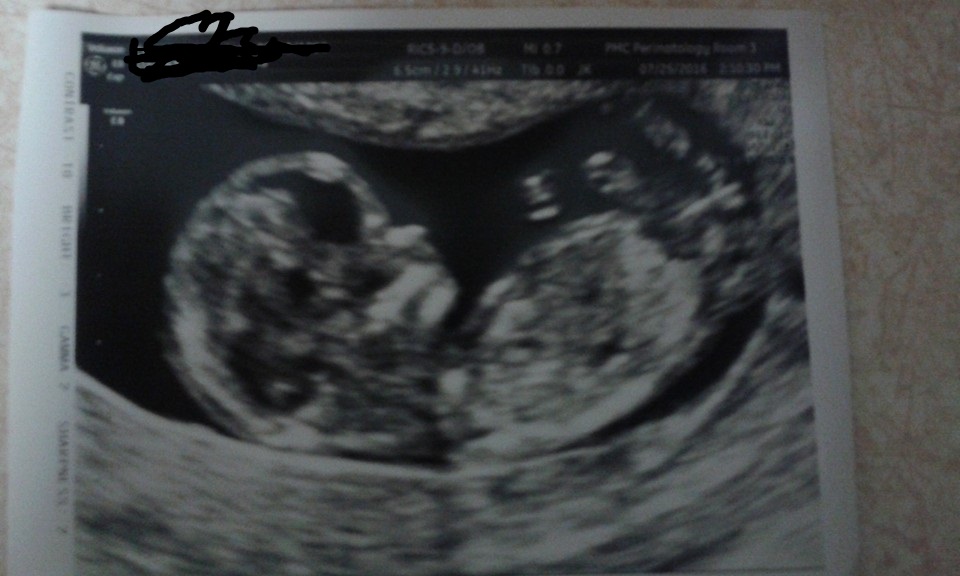

This is a 12 week transvaginal ultrasound. Anyone have any guesses on the gender!? :)Attachment 32699

Nub theory - looking girly